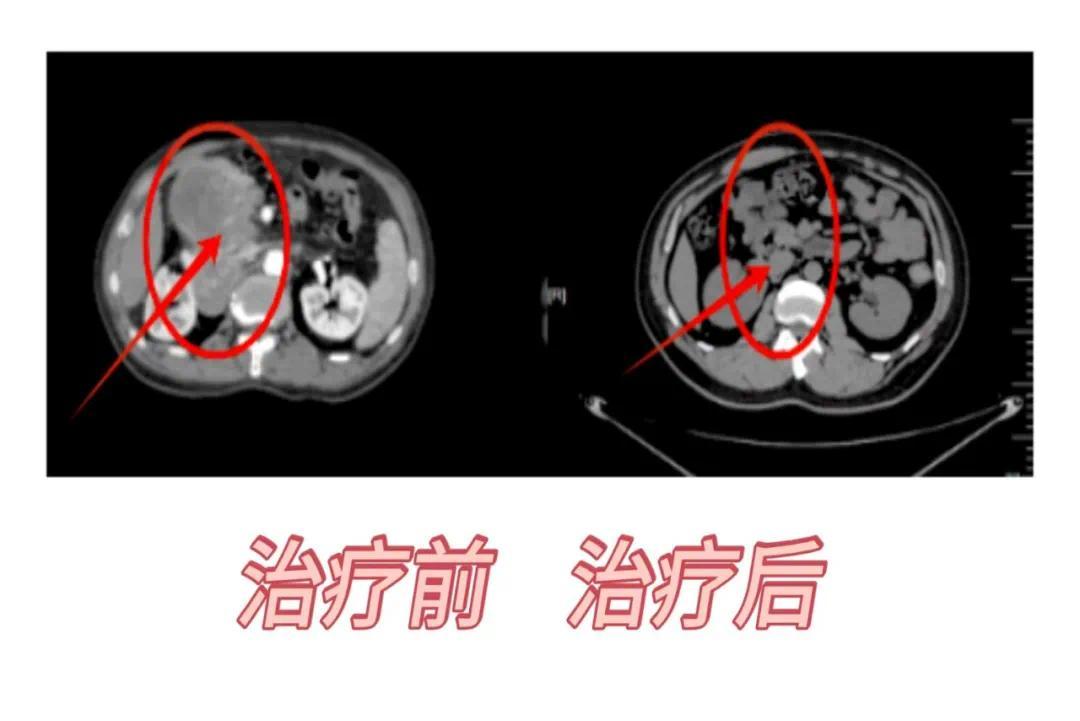

腹部治疗病例:腹部巨大肿瘤采用最先进的SFRT(空间分级治疗)技术,1年后复查病灶消失。